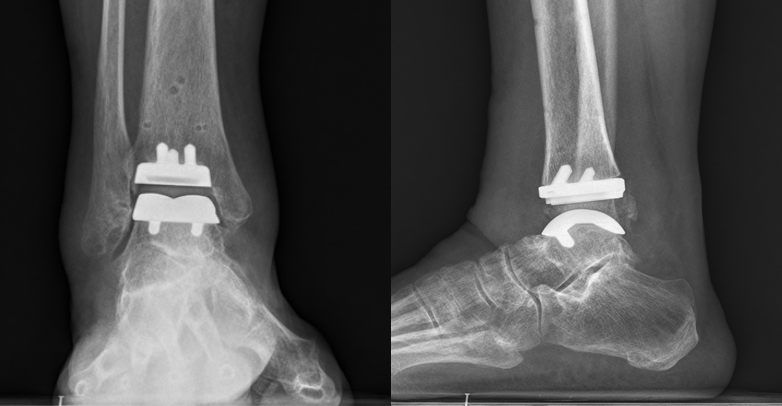

术前右踝关节片

术后复查右踝关节片